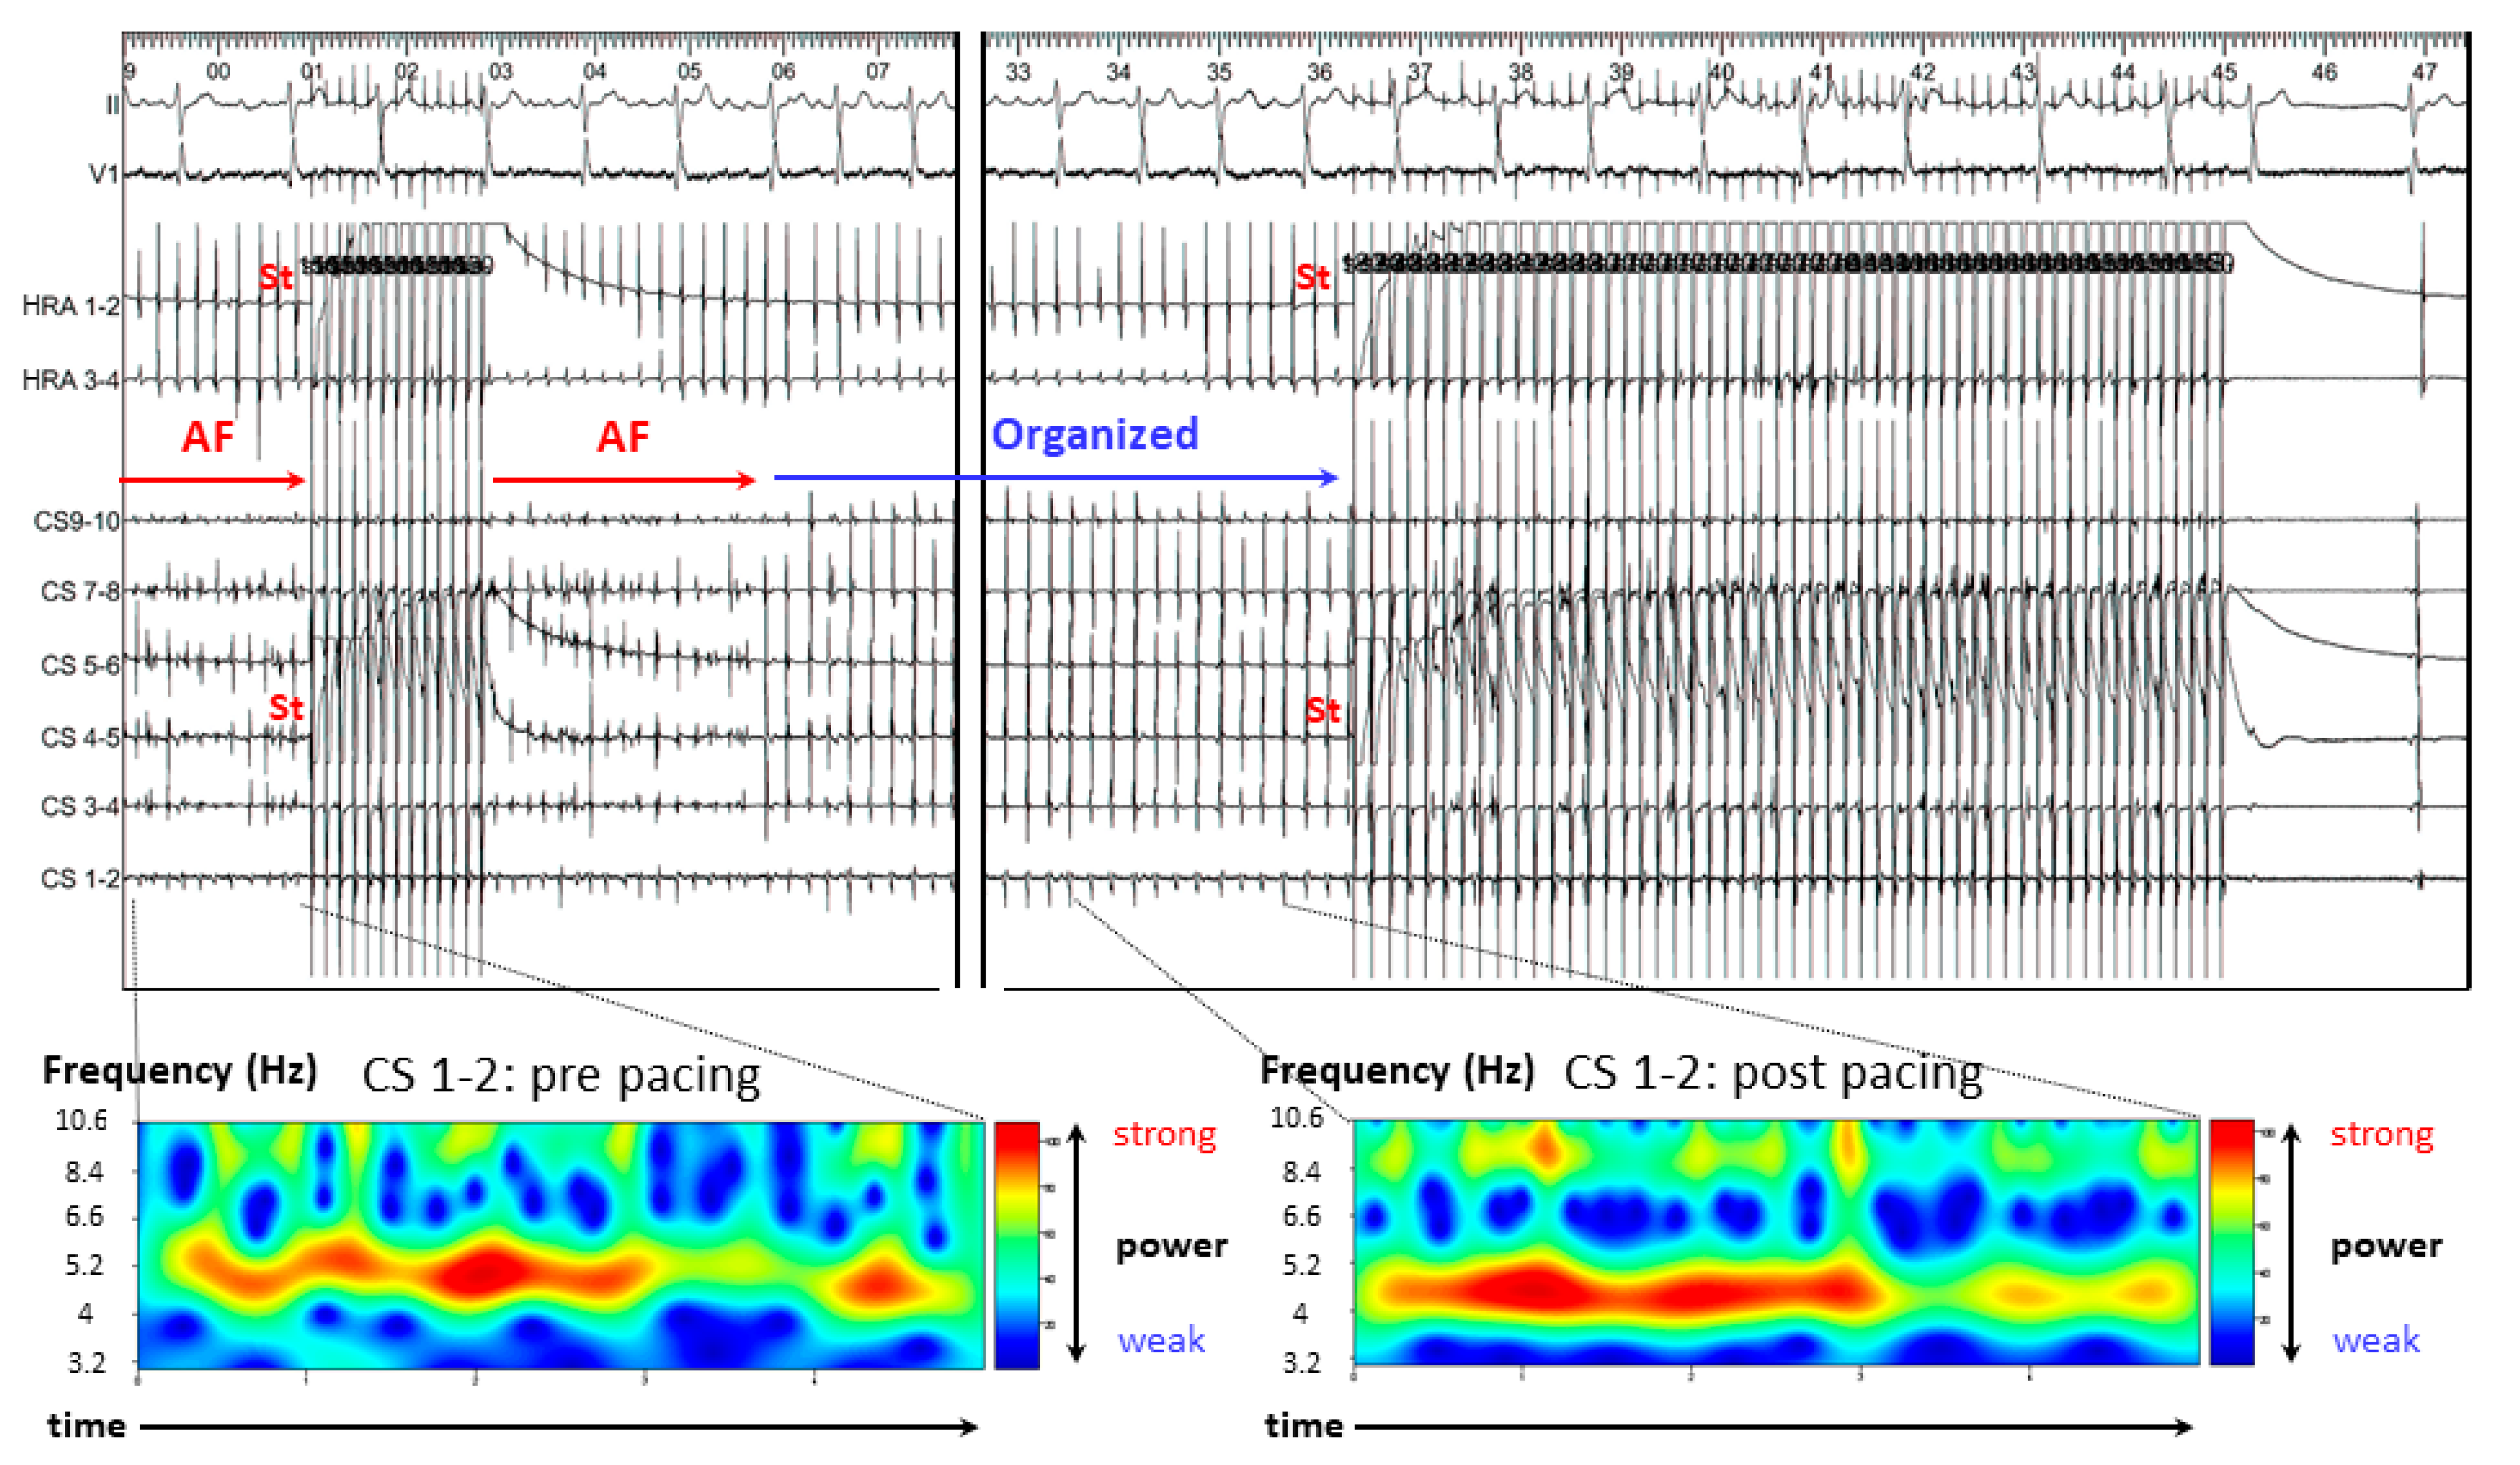

3.2.2. Case 2: 72-Year-Old Man with Symptomatic PAF